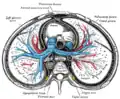

Secção transversal do tórax, mostrando as relações das artérias pulmonares.

Secção transversal do tórax, mostrando as relações das artérias pulmonares. -